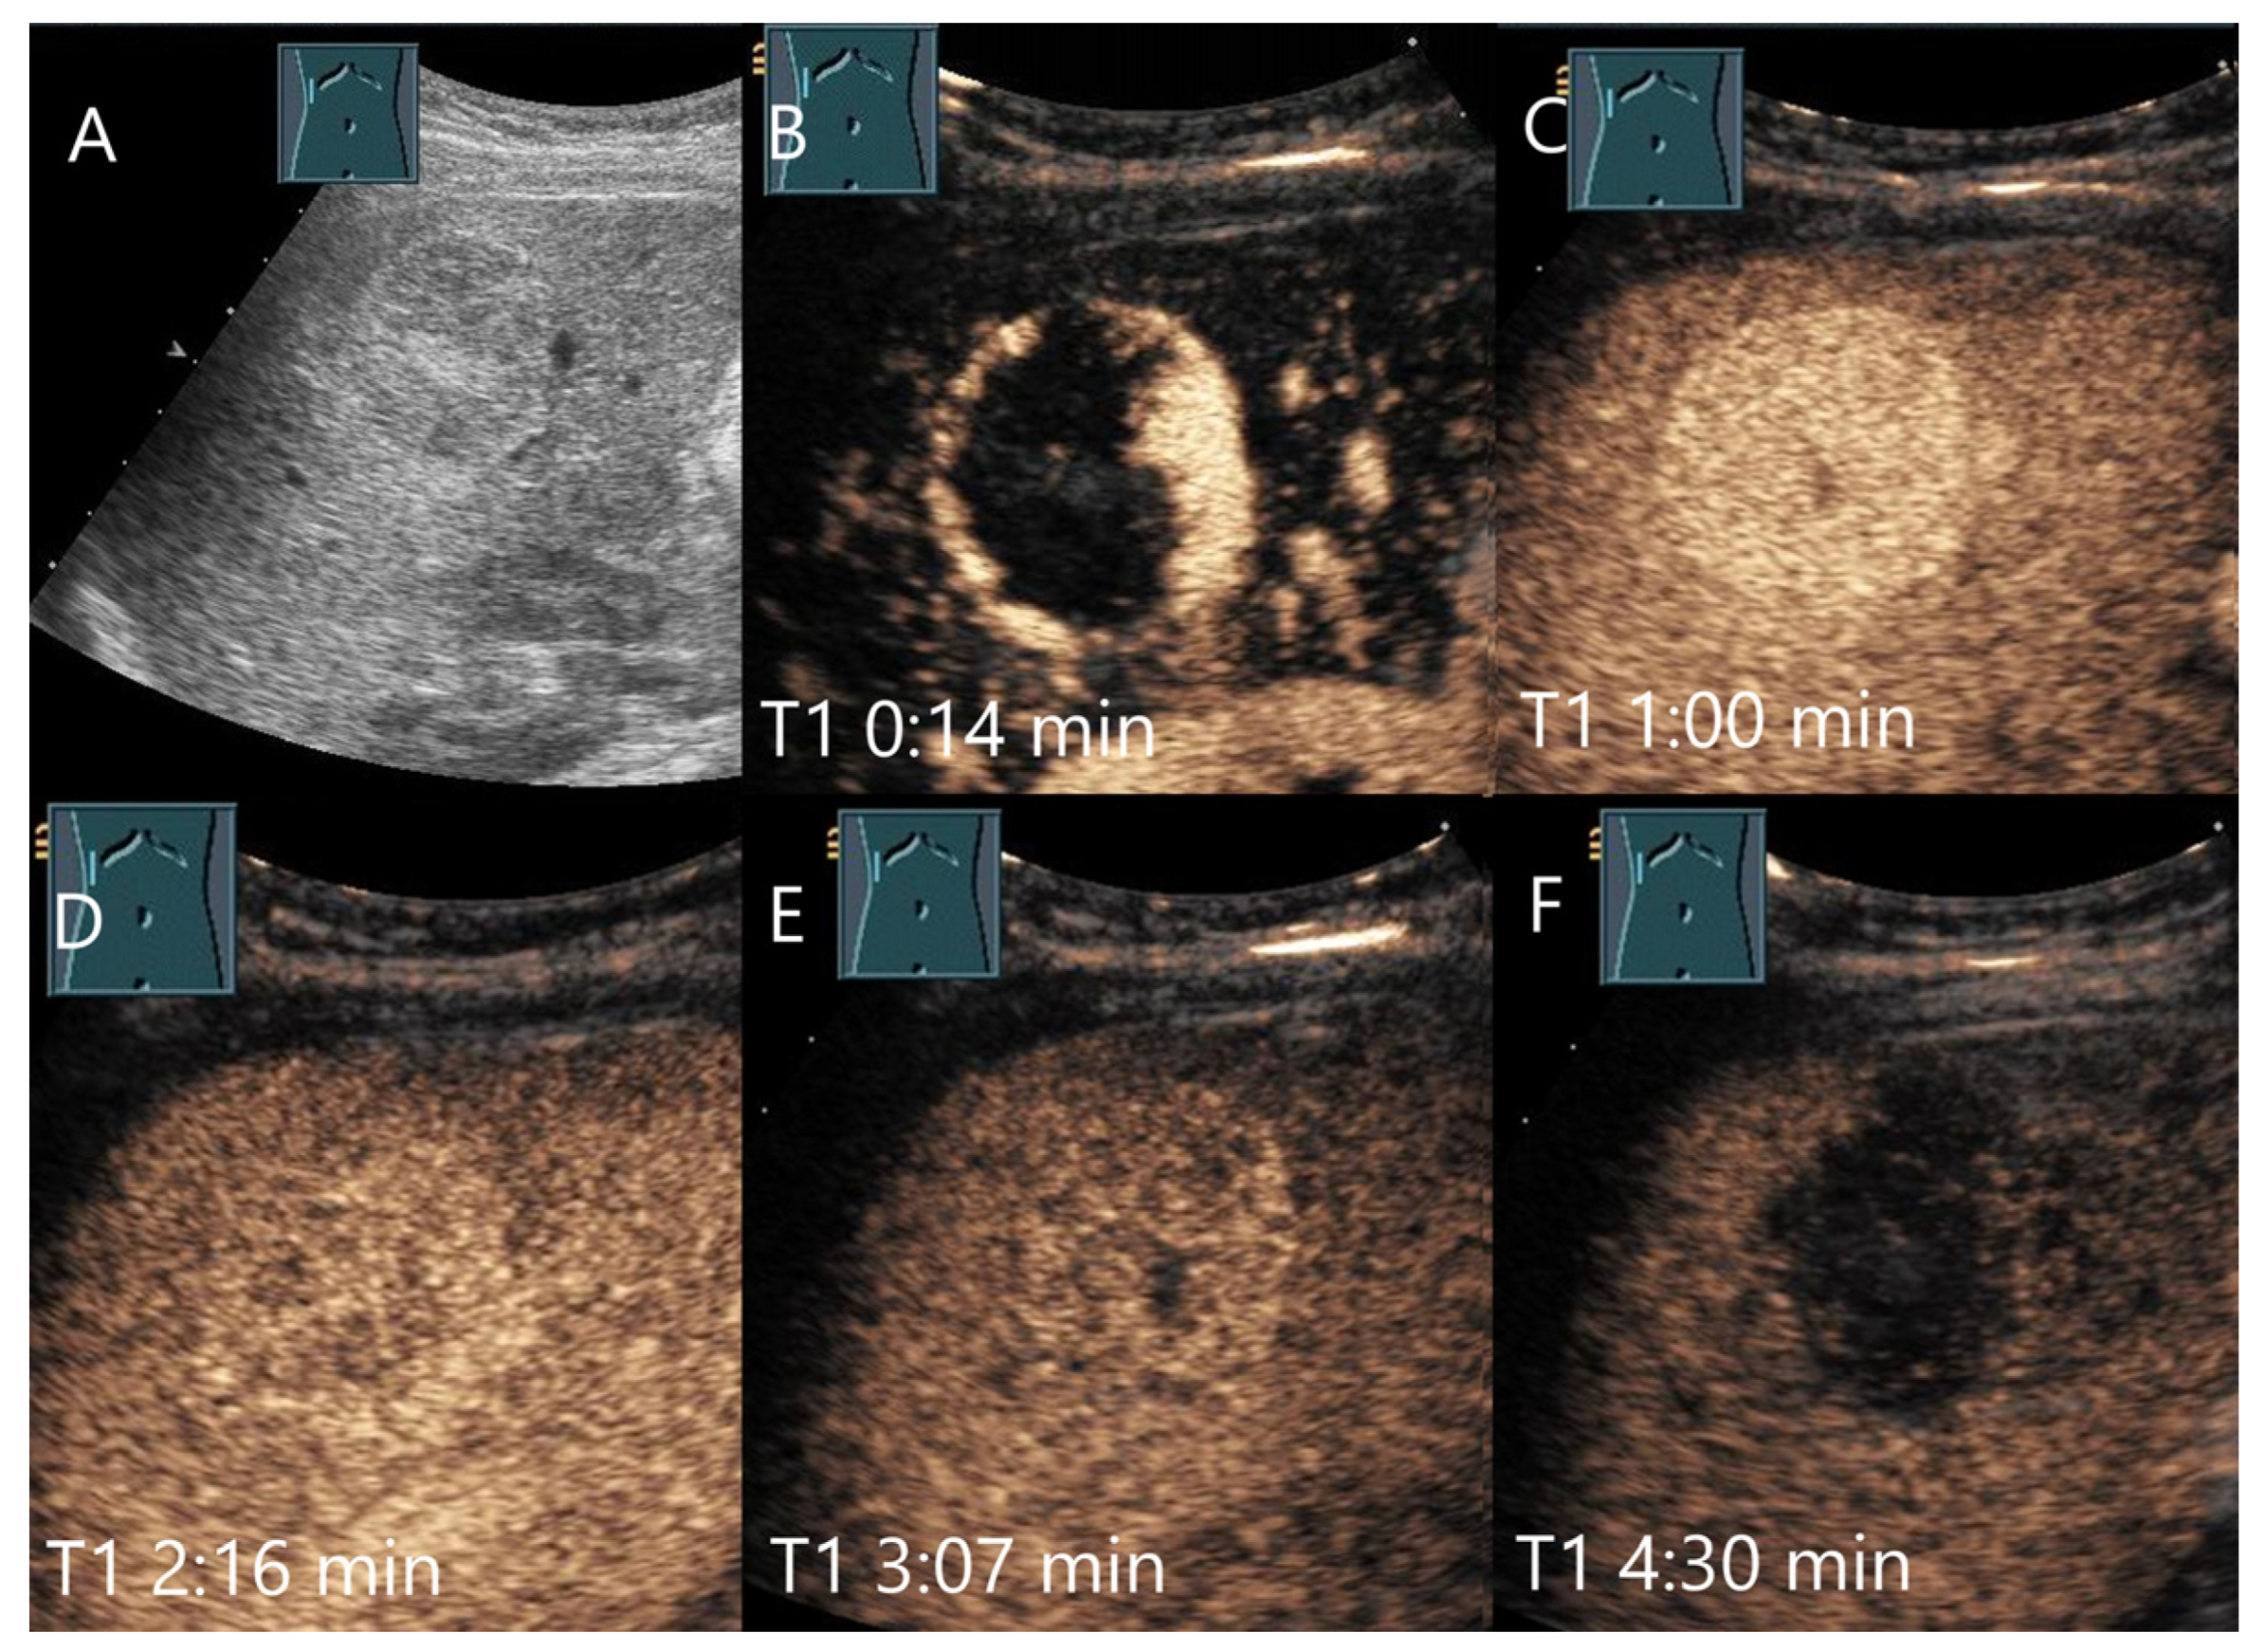

| FNH | Isoechoic, hypoechoic, sometimes hypoechoic rim. | Wheel spoke pattern, central artery, rarely peripheral artery and wheel. spoke pattern. Centrifugal filling | Hyperenhancement to isoenhanced, central scare. | Fibrosis and vascular obliteration. |